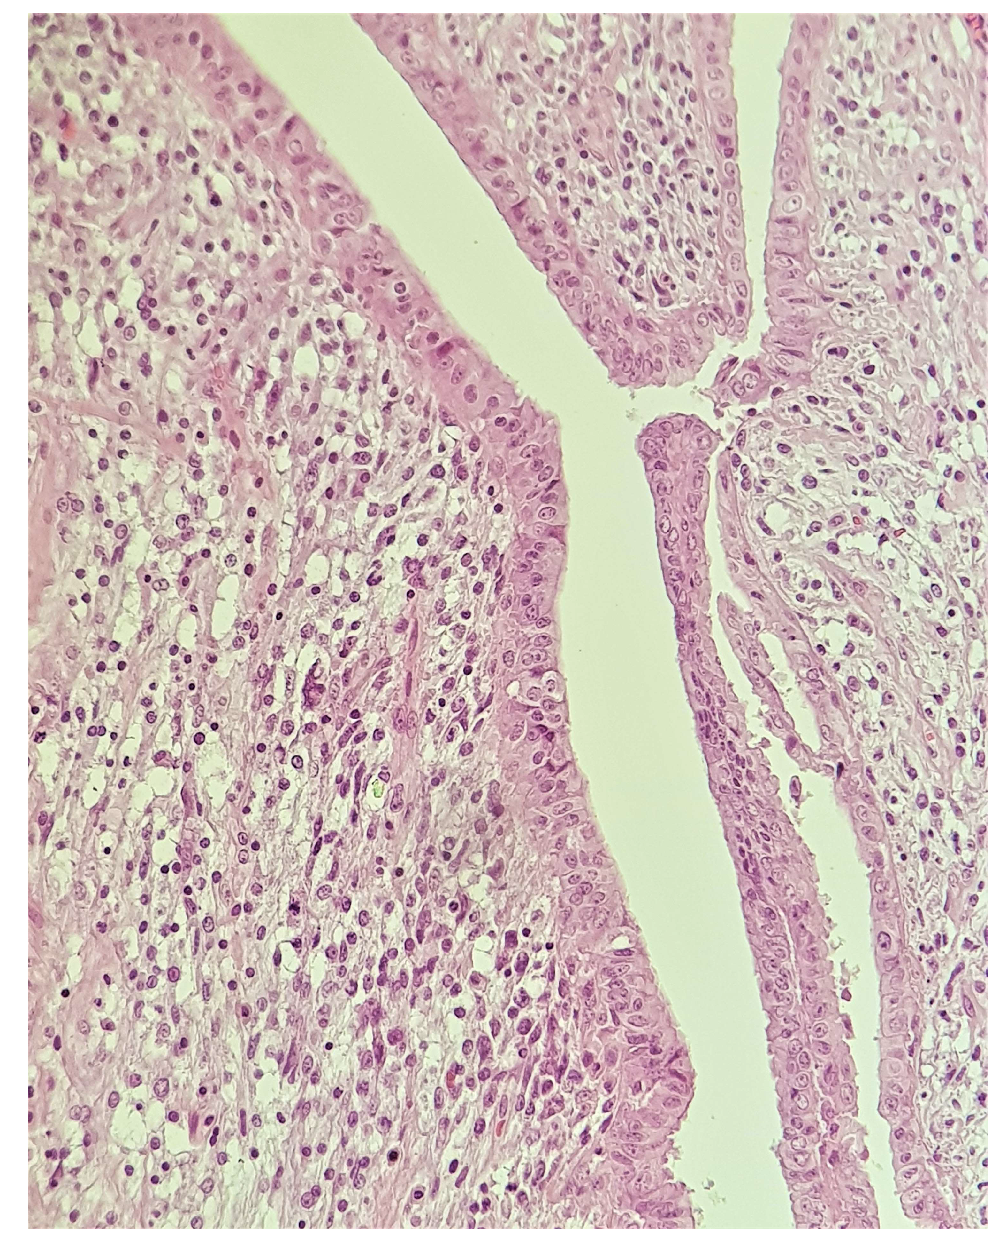

2. Case Presentation